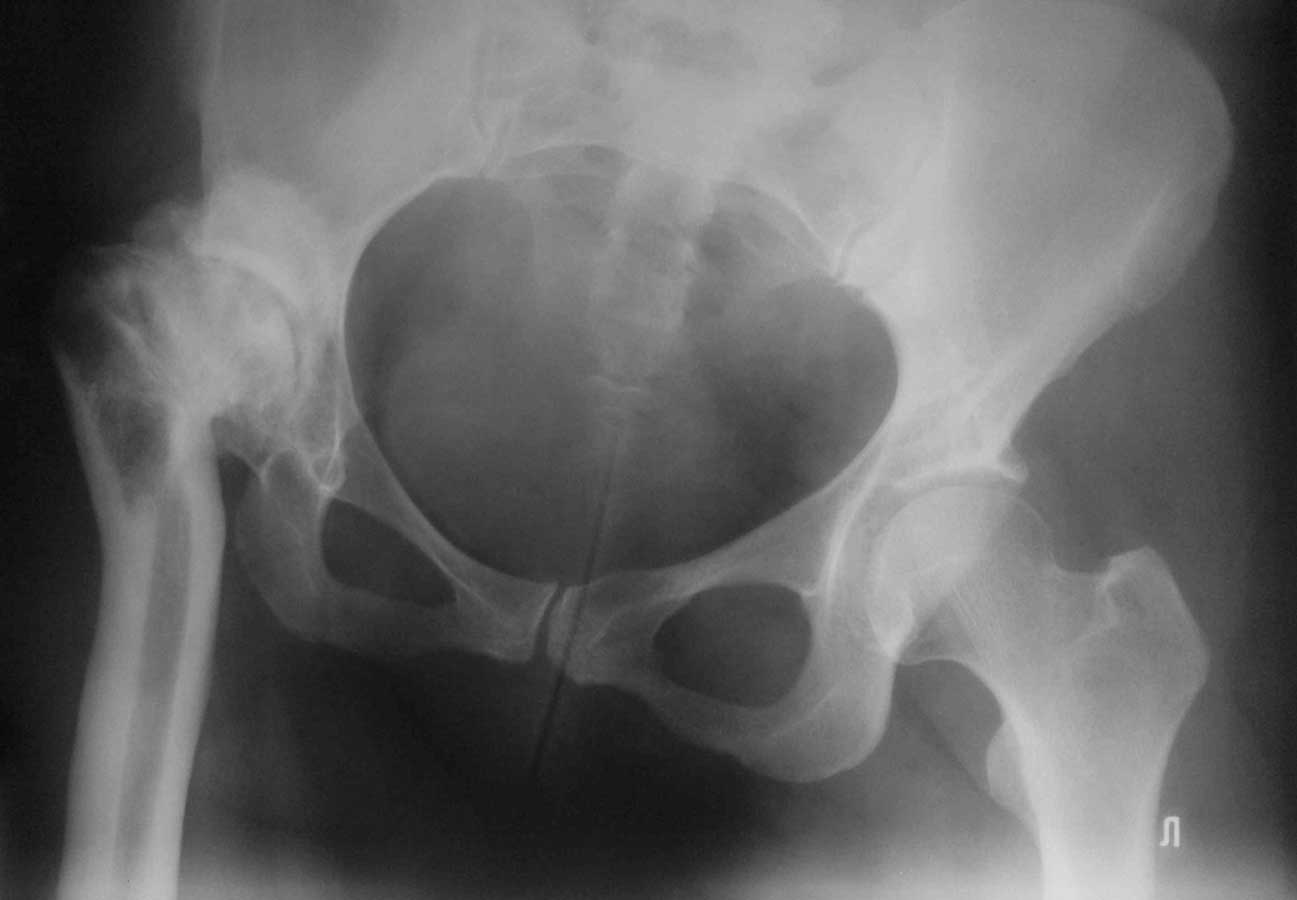

Уважаемые коллеги, к нам поступила женщина 45 лет с такой вот ситуацией:

Операция около 1,5 месяцев назад: тотальное б/ц эндопротезирование с остеотомией проксимального отдела бедра. Послеоперационный период - без особенностей, рана зажила первично, выписана домой. В анамнезе в детском и юношеском возрасте несколько оперативных вмешательств на вертлужной впадине и бедре по поводу врожденного вывиха бедра, судя по рубцам, протекавшие не совсем гладко.